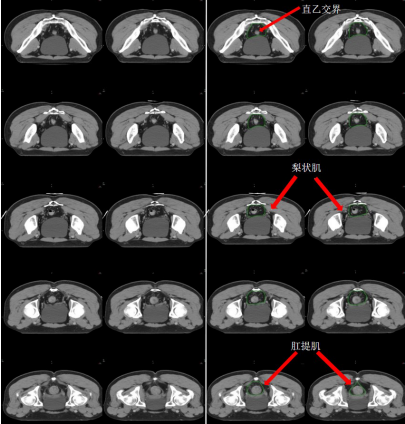

b) 直腸系膜區-M(深綠) (圖 7),邊界:

上界:腸系膜下動脈分叉為乙狀結腸動脈與直腸上動脈處/直乙交界;

下界:肛提肌插入外括約肌處/直腸周圍系膜脂肪組織消失處;

前界上:直腸上動脈前緣擴 0.7 cm;

前界中/下:直腸系膜筋膜,前方盆腔器官的后界;

后界:盆腔骶前區的前界;

外界上:側方、髂外淋巴結區的內側;

外界中:直腸系膜筋膜,側方淋巴結區的內側;

外界下:肛提肌內側緣。

圖 7  直腸癌直腸系膜區 CTV 勾畫示例